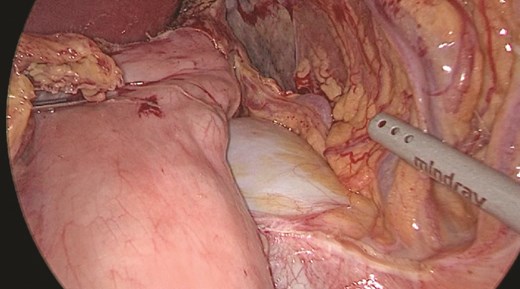

Multidisciplinary discussion was held to evaluate the most appropriate course of action for the patent condition, and the consensus was reached to pursue embolization as a first intervention. Embolization was performed by interventional radiology with no complications post-procedure, and the patient was optimized prior to her procedure. Patient was taken to the operating room in stable conditions. The spleen was enlarged around 20 cm. Inferiorly, the omentum and part of the transverse colon was attached to the spleen (Fig. 3), so we freed the omentum from the splenic tissue. The dissection continued until reaching short gastric vessels and entering the lesser sac (Fig. 4). Once the lesser sac was entered, the splenic vessels were identified (Figs 5 and 6), the splenic vein was hugely dilated with multiple collateral branching vessels at the hilum. Gaining posterior mobilization of the vein was challenging. The splenic artery was tortuous from the insertion around itself (Fig. 7). After complete mobilization of the fundus, we elected to divide each vessel starting with the splenic artery so we can achieve full mobilization of the vein (Fig. 9). After controlling the splenic artery, the splenic vein was dissected proximal to the splenic hilum (Fig. 8). It was hugely dilated and its wall is thickened secondary to AV fistula. It was difficult to achieve circumferential dissection, so we decided at that moment to convert to laparotomy to complete ligating the vein and to retrieve the specimen (Fig. 10a and b).

The spleen inferiorly, attached to it the mesentery and the transverse colon.